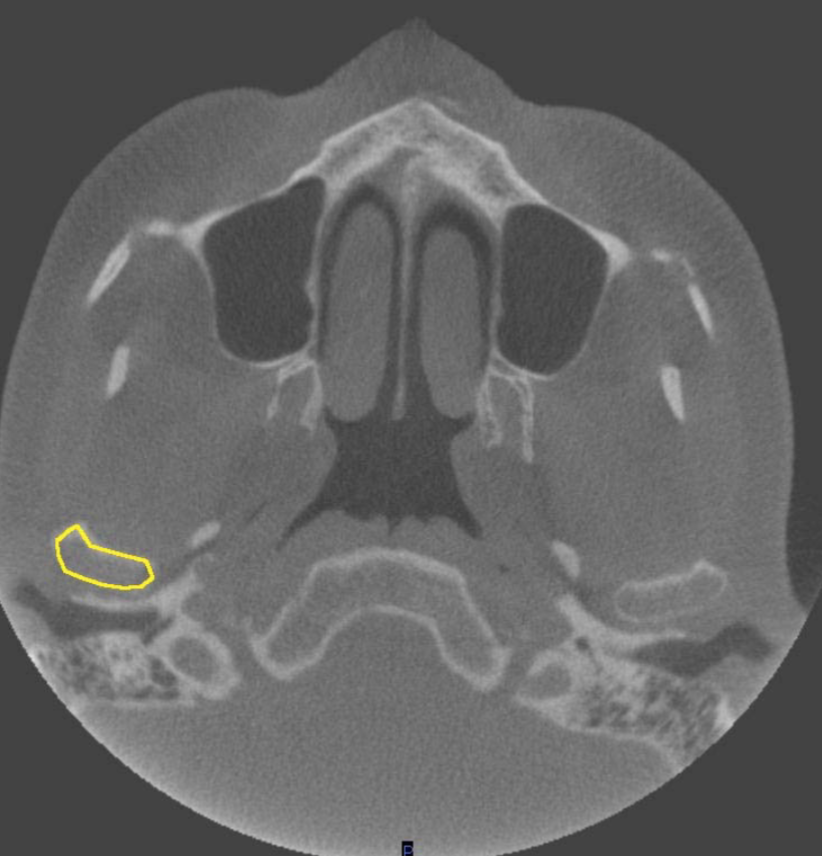

zygomatic arch

what is indicated by the YELLOW